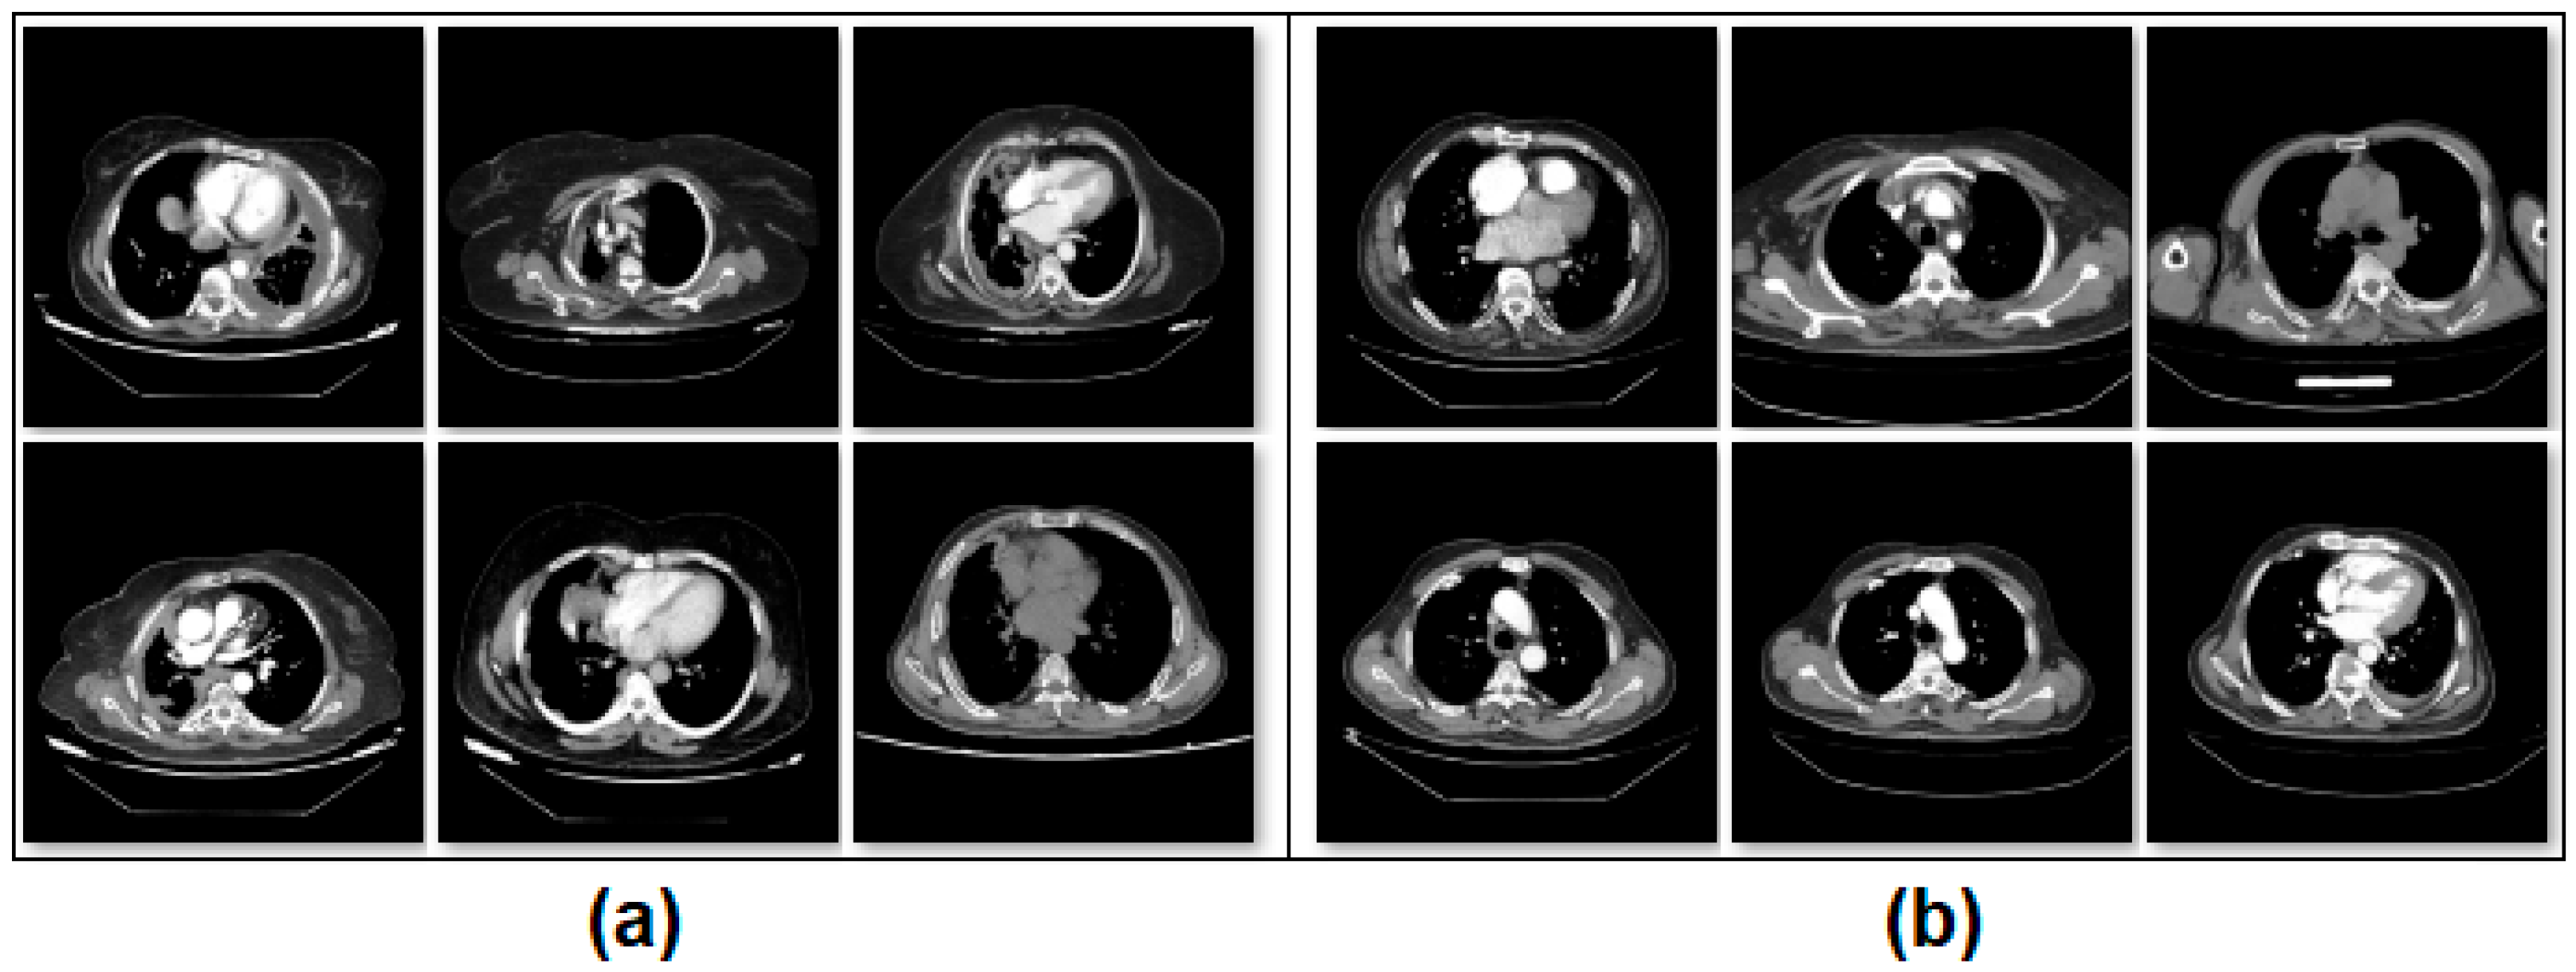

2.1. CT Image Dataset